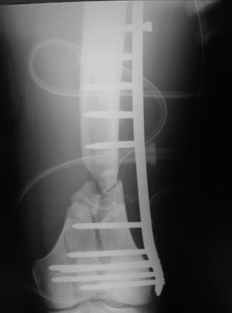

Re: Open supracondylar femur fx

This is what we have done... As generally true for LISS look at the bone not the hardware.

There are two more srews above. The one not completely in got damaged head.